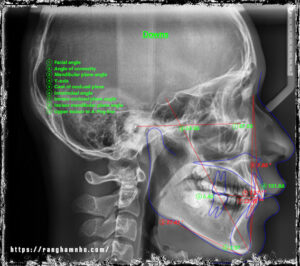

Tran Van Phu_2000: Class I crowding, miss #22. Extraction #31

Bệnh nhân nam sinh năm 2000, đến khám do tình trạng thiếu răng, nụ cười [...]